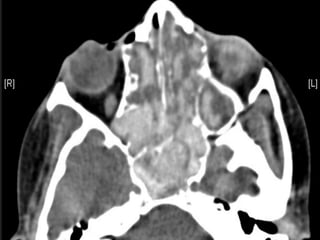

๏‚ง Usually unilateral

๏‚ง Well defined, high attenuation mass

f ๏‚ง Usually unilateral ๏‚งInvolves the maxillary sinus ๏‚ง Well defined, high attenuation mass ๏‚ง Occasional flocculent Ca ๏‚ง Reactive sclerosis of sinus wall ๏‚ง No invasion Fungal ball